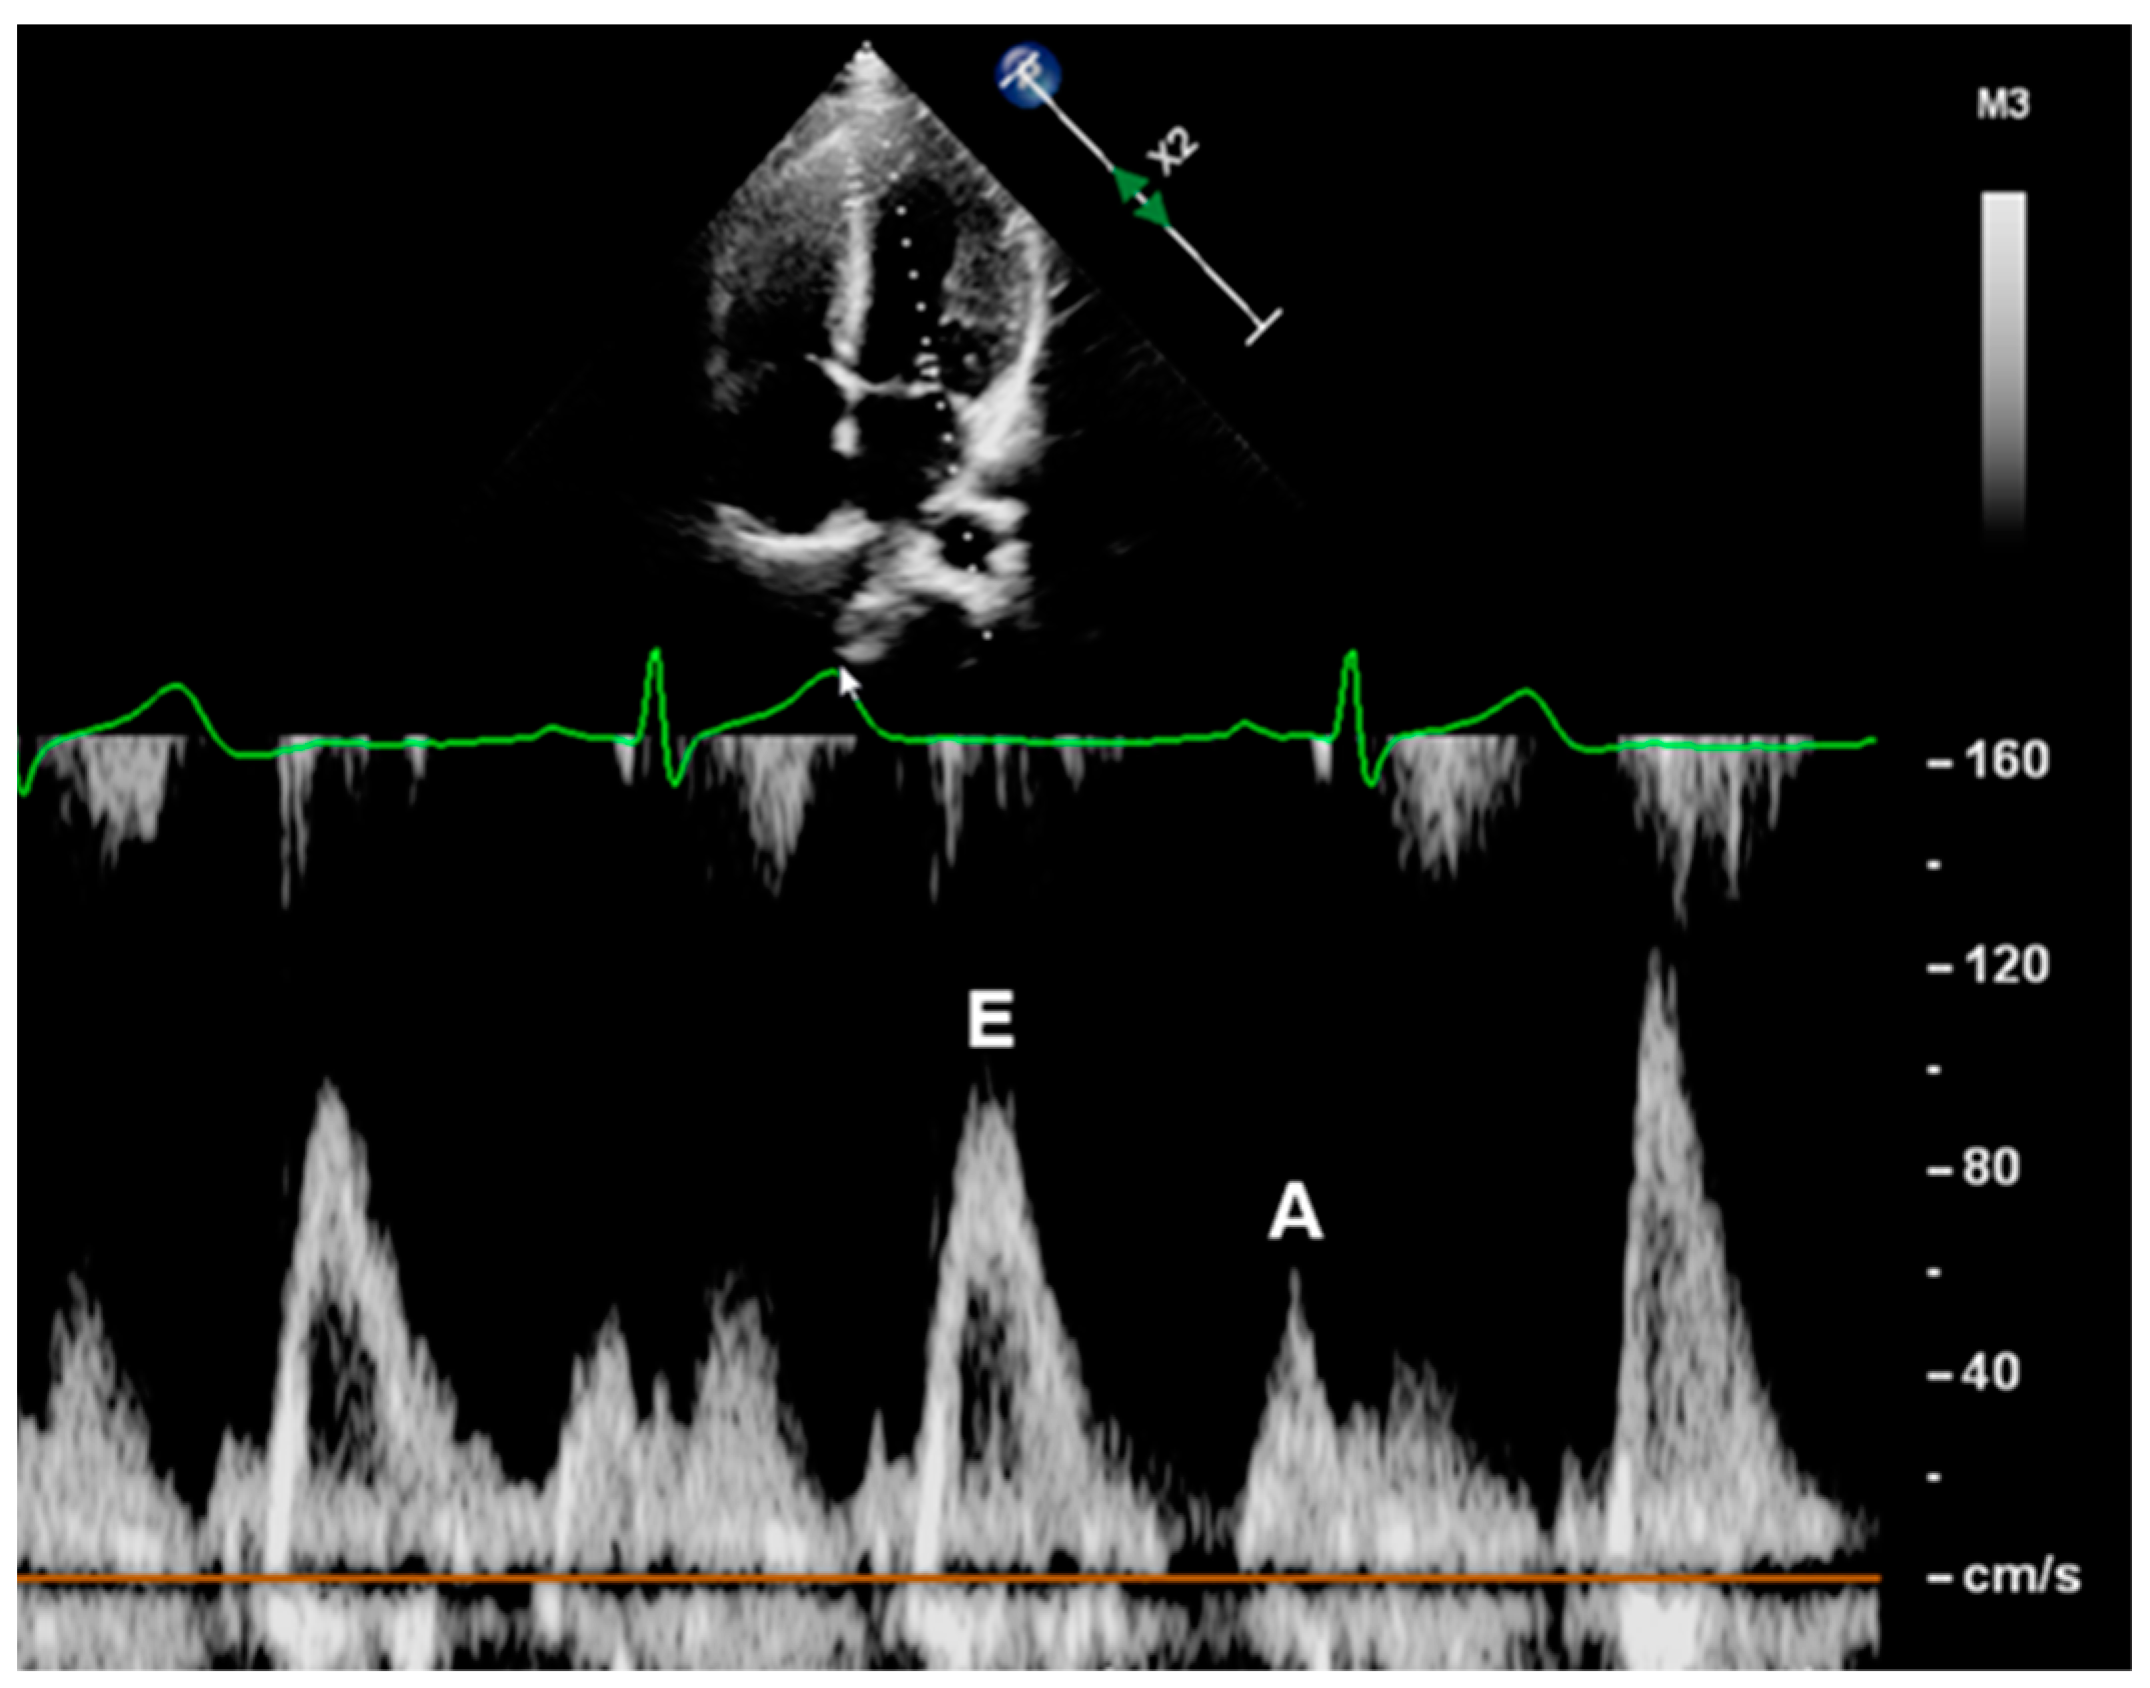

2.3.2. Mitral Inflow Velocities

| Mitral Inflow Velocities | ||||

| E (cm/s) | 99.82 ± 13.86 | 98.91 ± 15.46 | 0.703 | >0.999 |

| A (cm/s) | 50.44 ± 10.48 | 47.87 ± 10.83 | 0.145 | 0.225 |

| E/A | 2.05 ± 0.48 | 2.16 ± 0.54 | 0.220 | 0.297 |

| E (cm/s) | 99.49 ± 14.32 | 100.69 ± 17.43 | 0.719 | >0.999 |

| A (cm/s) | 49.84 ± 11.18 | 51.16 ± 10.68 | 0.575 | 0.782 |

| E/A | 2.08 ± 0.50 | 2.03 ± 0.44 | 0.601 | 0.879 |